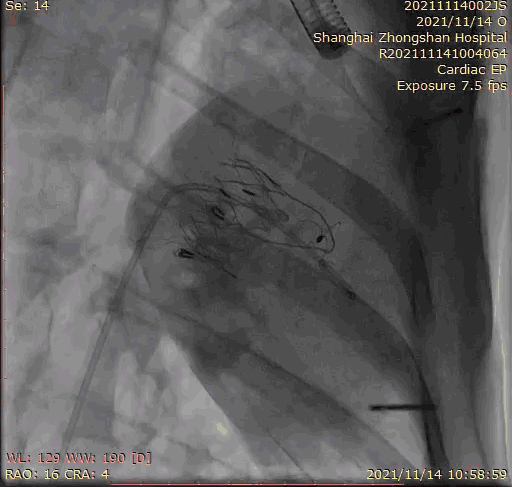

2021年11月14日星期日,复旦大学附属中山医院(以下简称中山医院)葛均波院士团队成功应用经血管介入三尖瓣置换产品Lux-Valve Plus完成临床前研究,并获得圆满成功!此次研究的成功预示经血管三尖瓣产品Lux-Valve Plus已完成临床前准备,即将开启后期的正式临床研究!

上海中山医院葛均波院士、钱菊英院长、周达新教授、潘文志教授、潘翠珍教授、李伟教授共同完成此次临床前研究。术后葛均波院士对Lux-Valve Plus的器械操作性能给予了高度评价,DSA和超声影像也显示出在本次研究中Lux-Valve Plus的安全性和有效性俱佳。

本次临床前研究经右侧颈静脉置入LuX-Valve Plus输送系统可调弯鞘管,在DSA及超声引导下将人工三尖瓣瓣膜植入到原有三尖瓣位置,利用独特的锚定技术将人工瓣膜支架可靠固定在预定的位置。